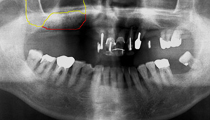

黄色と赤の線で囲まれた所に、サイナスリフトによって骨補てん材が注入されています。

サイナスリフト実施7ヶ月後、インプラント埋入を行いました。